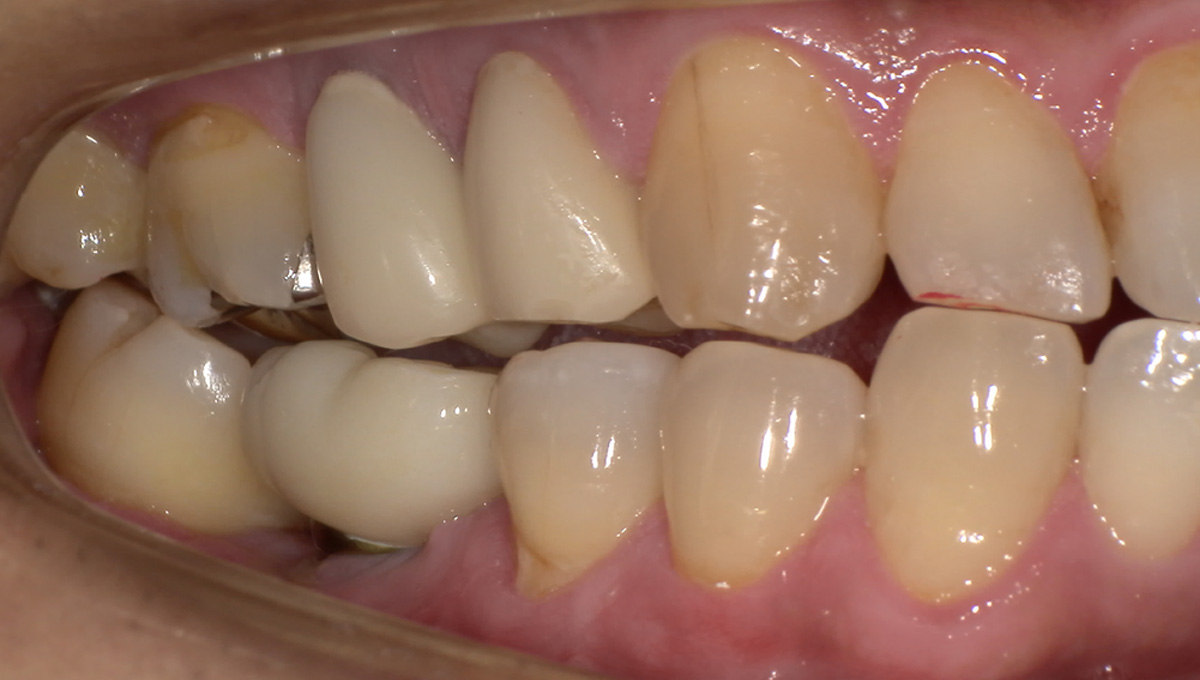

抜歯した箇所にインプラント治療を行った例

術前・術後の比較

初診時

歯が割れていて、痛みがあり、抜歯となりました。

パノラマレントゲン写真 -

インプラント手術から3ヵ月後、型どりをして、仮歯を製作しました。

仮歯の調整期間を経て、セラミックの歯が入りました。

レントゲン画像 治療前 インプラント治療後